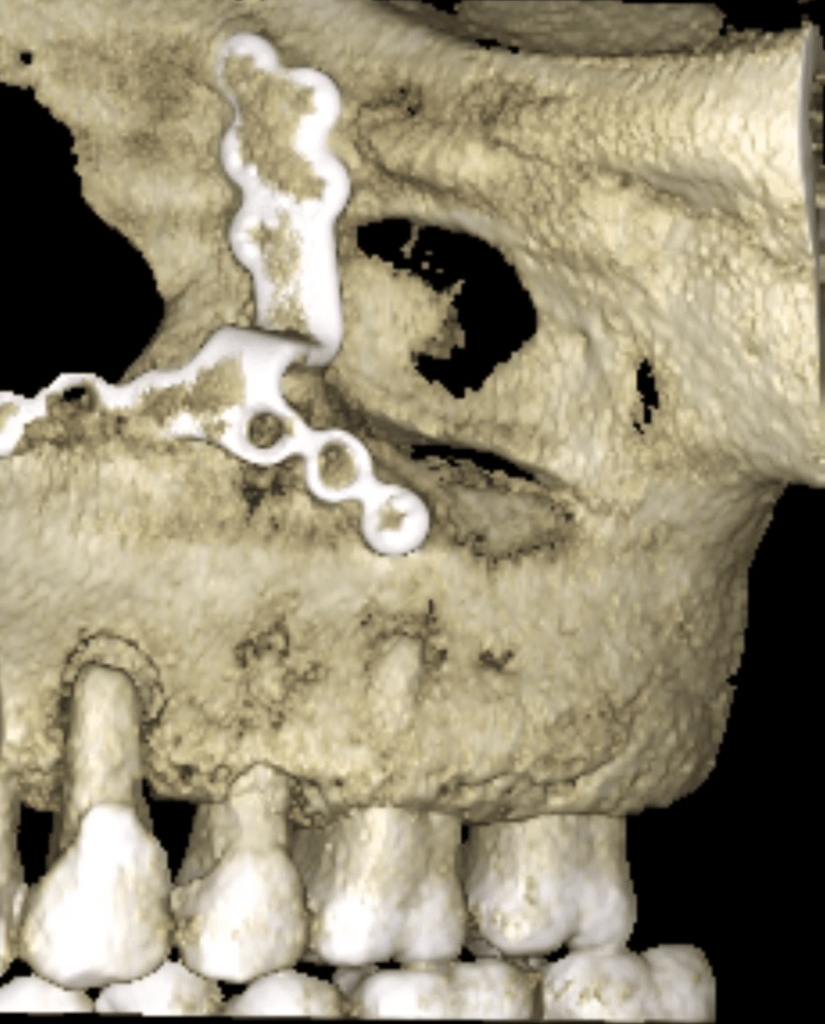

Vertical root fracture